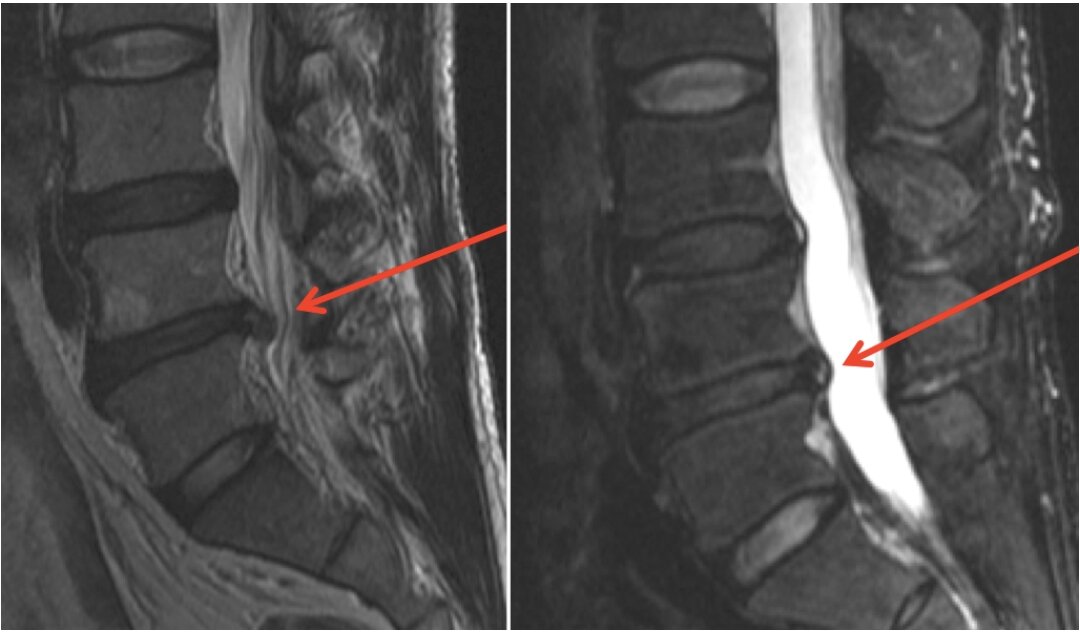

Prior to the scan, the patient filled out a routine MRI patient safety questionnaire which did not reveal any apparent contraindication to MRI. Following the MRI scan, an examination of the finger was carried out. There was no obvious sensory-motor deficit, and no soft tissue or joint pathology was palpable. A plain radiograph of the right hand revealed a 2 cm metallic spike on the ulnar aspect of the right middle finger distal phalanx (). It is thought that the ferrous nature of the metallic spike caused it to vibrate under the influence of the MRI scan’s magnetic field, leading to finger pain. The patient was then referred to the plastic surgery team who removed the foreign body under local anaesthetic. She made an uneventful recovery with no functional or tissue loss.

x-Ray scan demonstrating a linear metallic foreign body in the right middle finger of an 82-year-old woman.